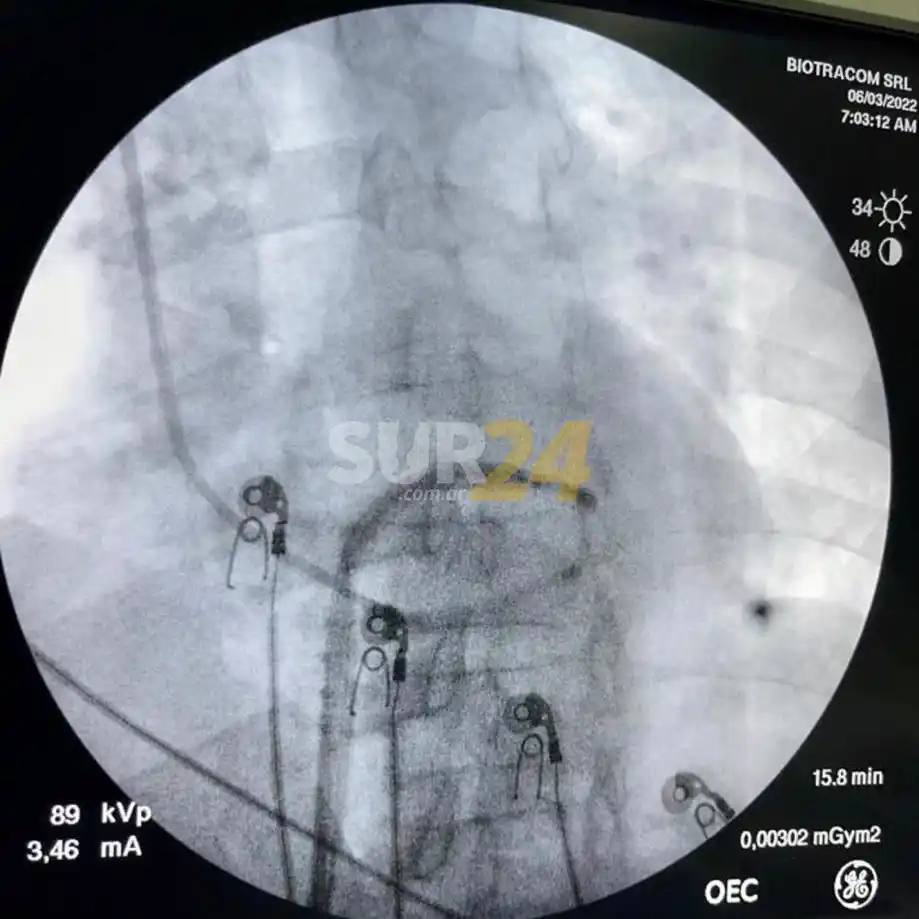

“Con esta condición, luego de muchas trabas, – continuó- la familia decidió confiar en realizarse una ablación por radiofrecuencia en Sanatorio San Martin S.A., donde se hizo la ablación por radiofrecuencia por abordaje transeptal del Wolff Parkinson White en forma exitosa”, mismo procedimiento hecho meses atrás.

:format(webp):quality(40)/https://sur24cdn.eleco.com.ar/media/2022/07/ablacion.jpg)